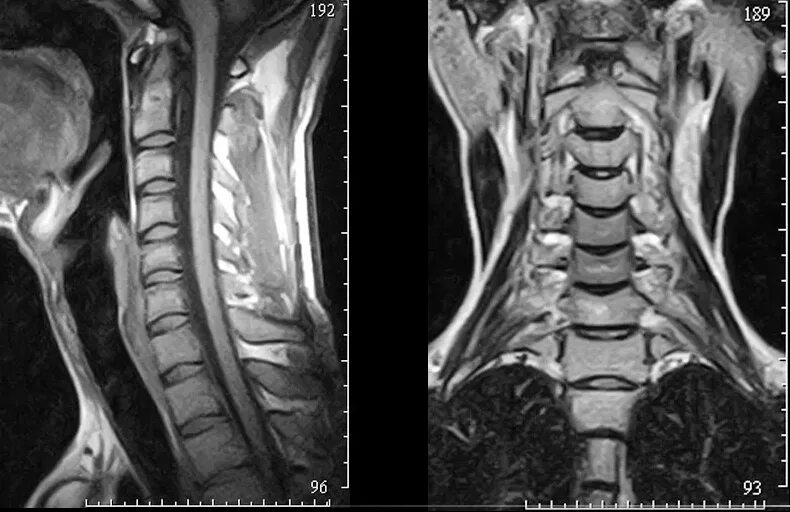

Мрт или кт позвоночника при болях